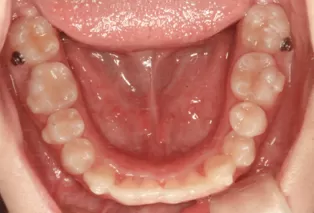

Intraoral photos